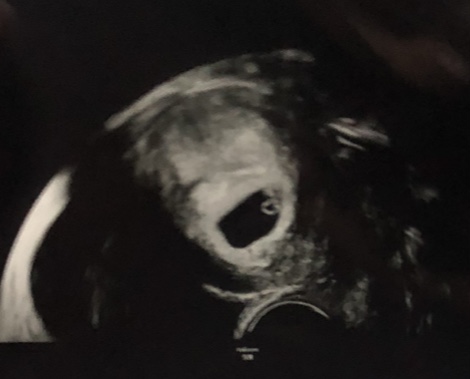

@katarinaforever ahoj, bijú 2 srdiečka, len prepazka medzi bábätkami je hrubá, vraj by to tak nemalo byt. Lekár mi nič bližšie nepovedal, podľa mna ma nechce strašiť, ibaže ma bude sledovať a ani na nete som nič nenašla… tak sa neviem ani úplne tešiť, pretože sa bojím.